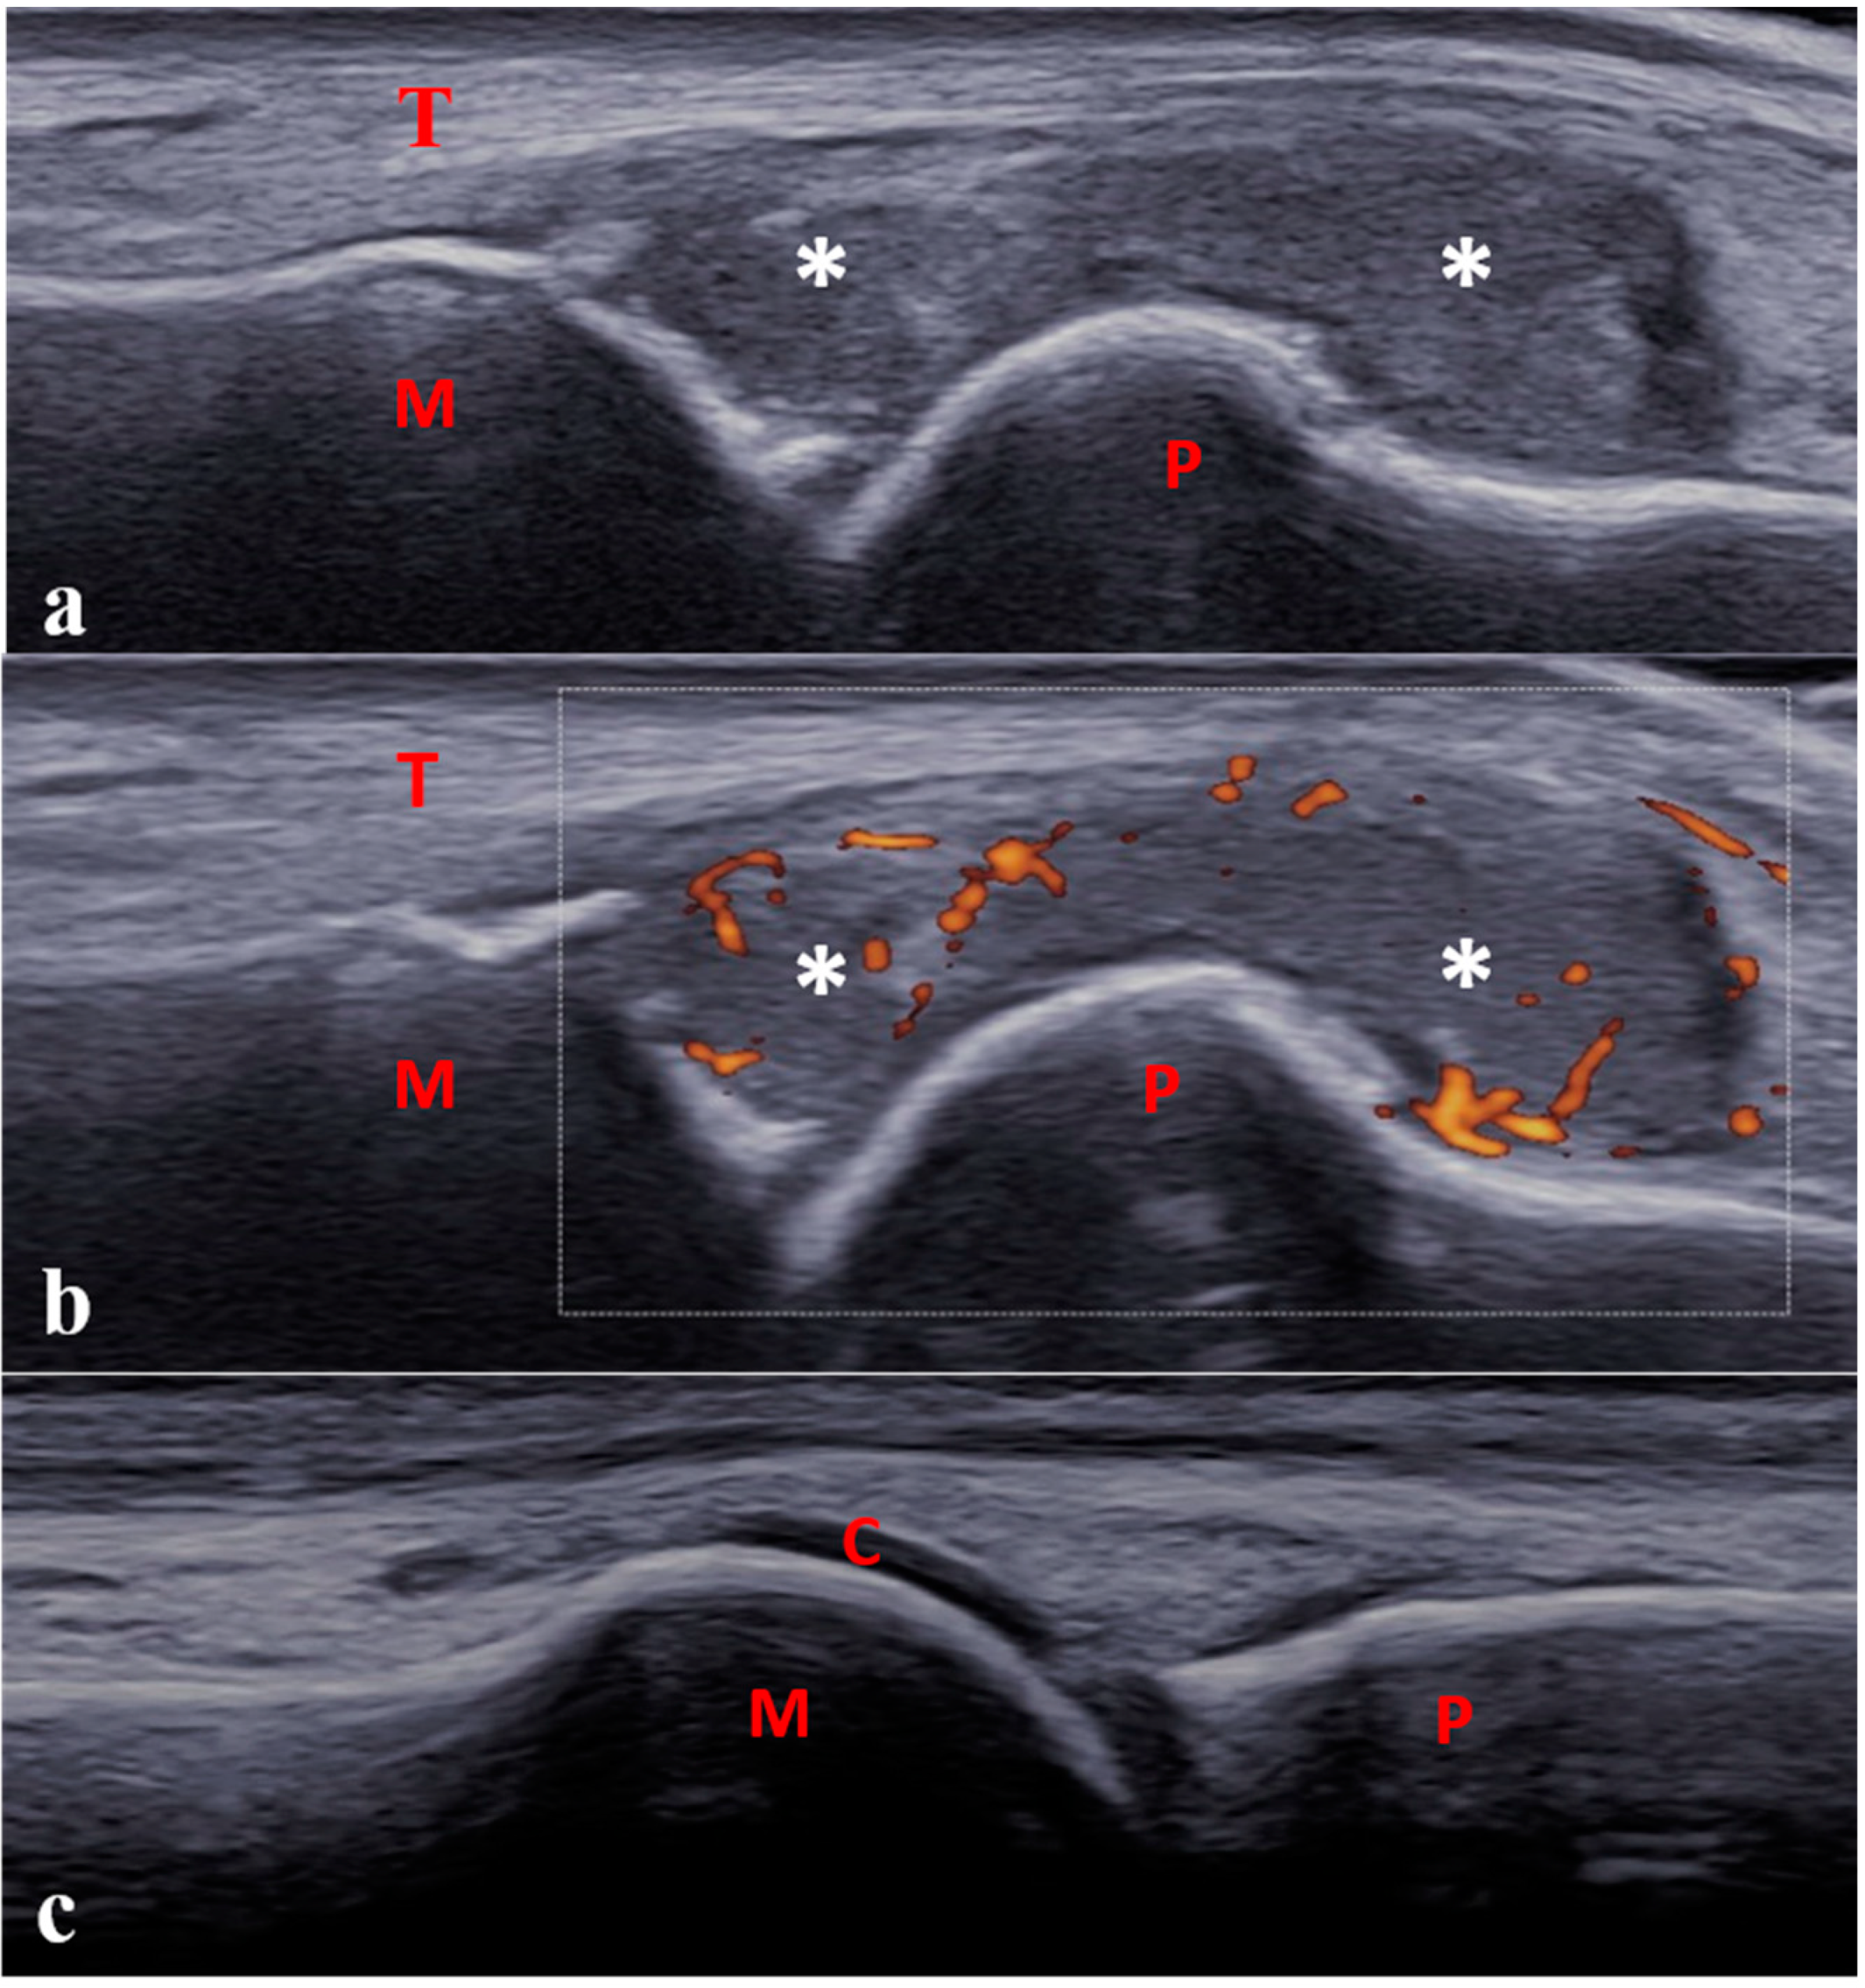

- Lanni, S.; Bovis, F.; Ravelli, A.; Viola, S.; Magnaguagno, F.; Pistorio, A.; Michele Magnano, G.; Martini, A.; Malattia, C. Delineating the Application of Ultrasound in Detecting Synovial Abnormalities of the Subtalar Joint in Juvenile Idiopathic Arthritis. Arthritis Care Res. 2016, 68, 1346–1353. [Google Scholar] [CrossRef] [PubMed]

- Collado, P.; Naredo, E.; Calvo, C.; Gamir, M.L.; Calvo, I.; García, M.L.; Merino, R.; Graña, J.; Bustabab, S.; Garrido, J.; et al. Reduced Joint Assessment vs Comprehensive Assessment for Ultrasound Detection of Synovitis in Juvenile Idiopathic Arthritis. Rheumatology 2013, 52, 1477–1484. [Google Scholar] [CrossRef]